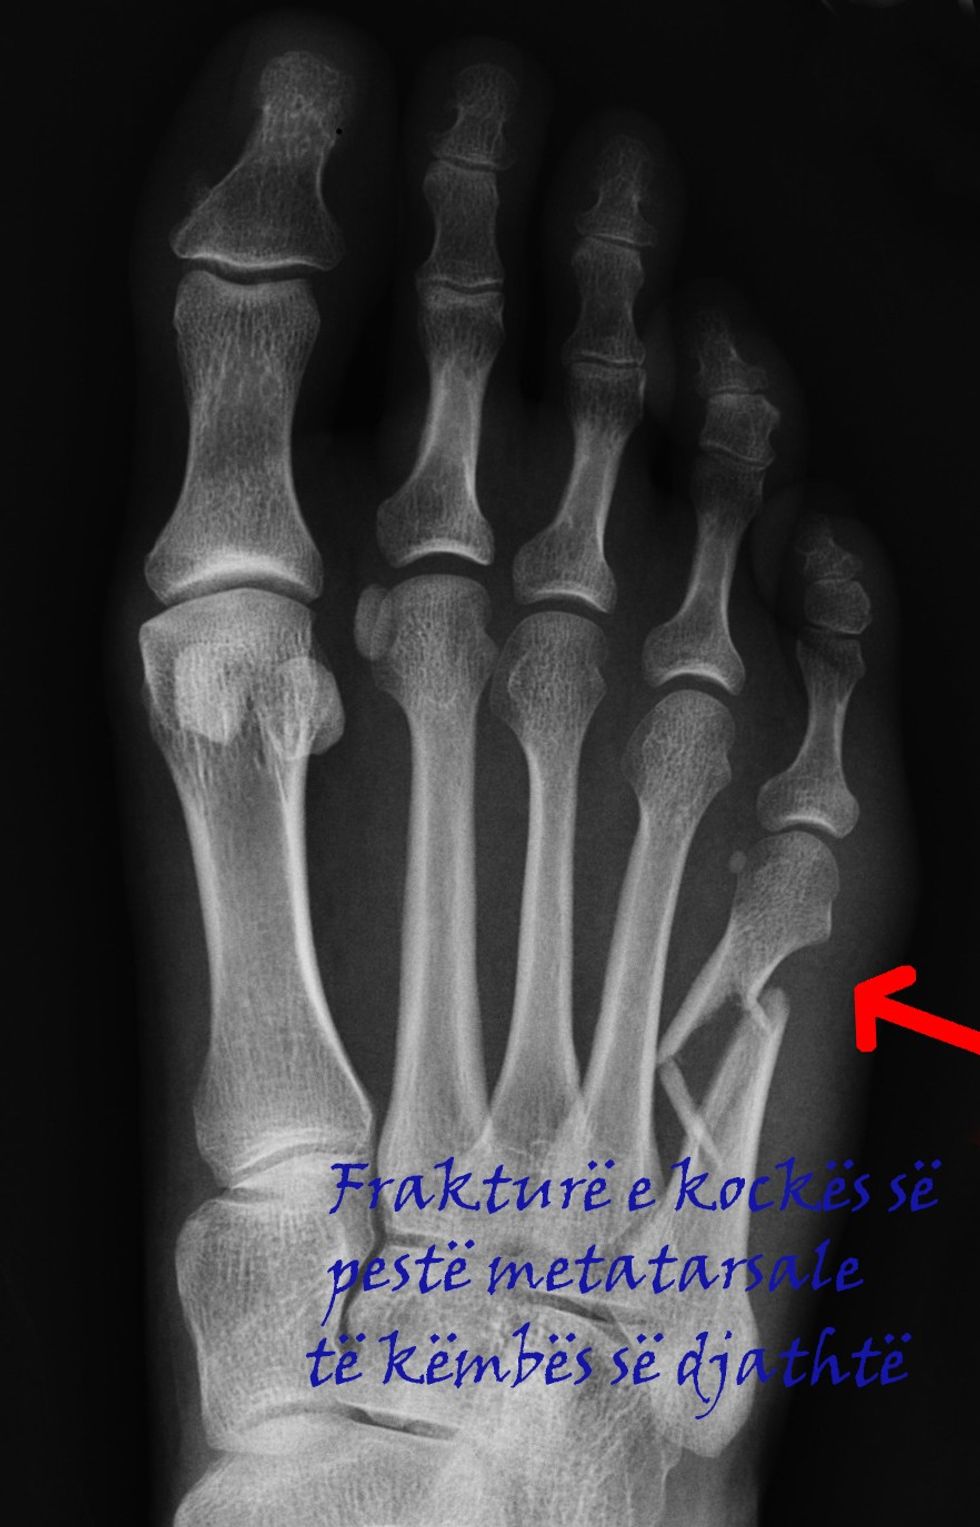

Frakturat e ashtit të pestë metatarsal

Frakturat (thyerjet) janë të shpeshta në ashtin e pestë metatarsal - ashti i gjatë në pjesën e jashtme të këmbës që lidhet me gishtin e vogël. Dy format më të shpeshta të frakturave që ndodhin në këtë kockë janë, fraktura me shkëputje të një pjesë të vogël të kockës dhe fraktura Jones, e cila mund të jetë stres-frakturë (që ndodh si pasojë e ngarkesës dhe veprimit të vazhdueshëm të forcës në të njëjtin vend) dhe frakturë e përnjëhershme si pasojë e traumës.

Kur nevojitet ndërhyrja Nëse si pasojë e lëndimit ka ndodhur zhvendosje e kockës, thyerje mulitple (më shumë se një fragment i thyer i kockës) ose nuk ka ndodhur shërimi adekuat - atëherë nevojitet ndërhyrja kirurgjike.